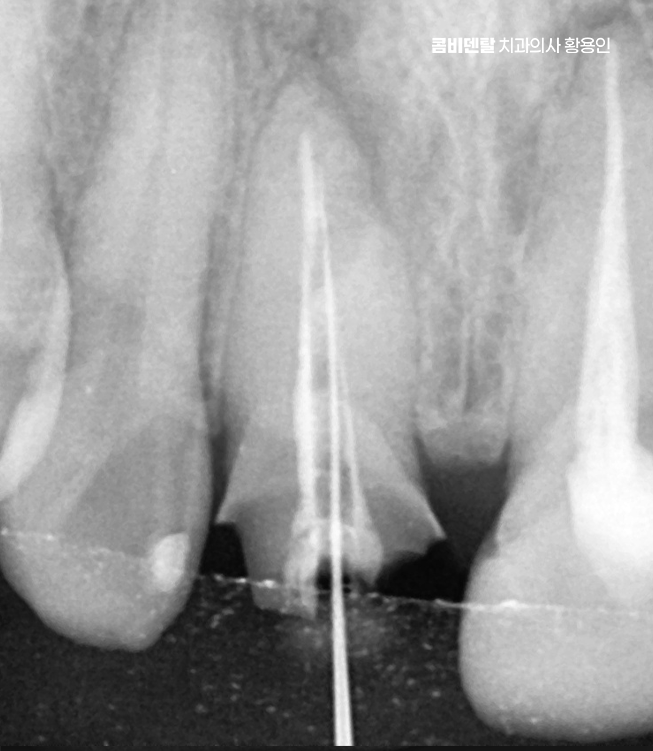

신경치료는 치아 내부의 염증이나 감염된 신경을 제거하고, 뿌리 속을 소독해서 밀봉하는 치료로 앞니는 뿌리가 하나인 경우가 대부분이라 어금니보단 비교적 간단하지만, 이미 보철을 한 치아는 구조적으로 약해져 있기 때문에 세심한 처치가 필요한데 뿌리 일부가 약해져 있거나 균열이 생겨 있을 가능성도 있어서 이런 경우엔 정밀한 신경치료가 필요하며 감염이 심한 경우엔 2~3회에 걸쳐 치료가 이뤄지고, 상태가 안정된 뒤에 마무리되는 거예요.

문제가 심해지면 결국 신경에까지 세균이 도달해서 통증이 생기고 찬물에 시리거나, 저리듯이 쑤시는 느낌, 잇몸에 작은 뾰루지가 생기는 경우도 있으며 그냥 손가락으로 눌렀을 때 묵직한 압통이 있다면 이미 신경치료가 필요한 상태일 가능성이 높아지고 이런 경우엔 기존 보철물을 제거하고, 내부 충치 상태를 확인한 뒤, 신경치료부터 들어가야 할 수 있었어요